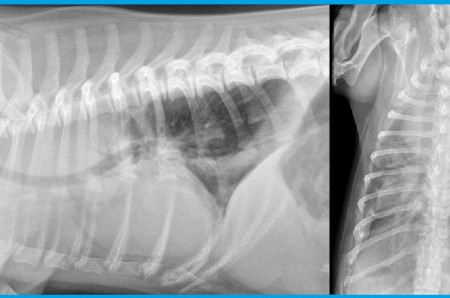

5-year-old Dachshund dog presented with acute respiratory distress, pale mucosa. Radiographic examinations: right lateral and dorsoventral projections.

Read more